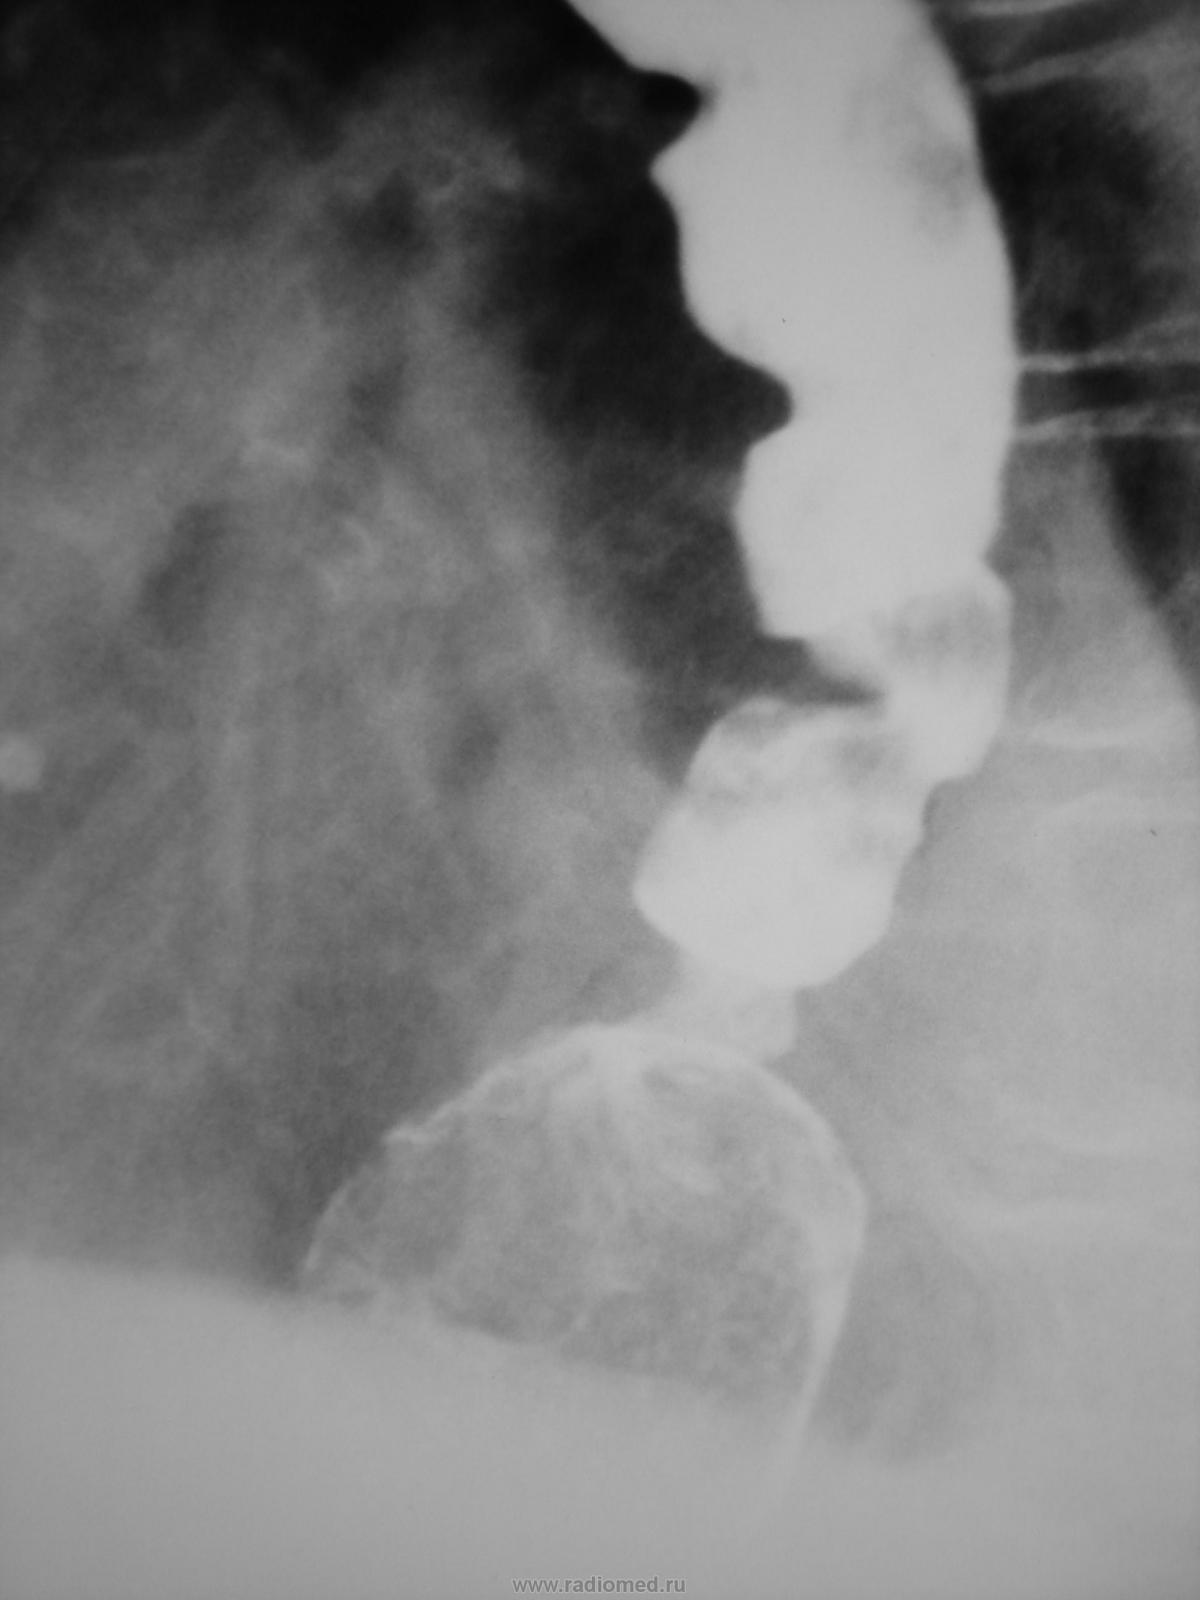

Пациентка 80 лет направлена на рентгеноскопическое исследование пищевода и желудка. 3 дня не может есть, т.к. даже при проглатывании воды возникает рвота.

Конечно думаю об "органике" + отсутствие газового пузыря желудка + по всей видимости, остатки пищи в дистальном расширенном отделе пищевода + перистальтические волны по контуру пищевода, который трудится, чтобы протолкнуть "содержимое" дистальнее, но без эффекта + отсутствие типичного рельефа обдоминального отдела пищевода. Снимки сделаны в положении стоя?